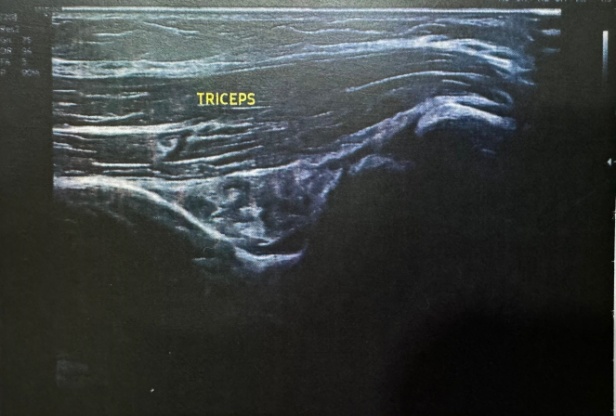

Fig. 1 Fig. 2

Fig. 3 Fig. 4

Fig. 1-6: Ultrasound image report

Ultrasonography of right elbow joint

No significant free fluid seen in elbow joint region.

The visualized cortex of distal humerus and proximal radius appears normal and show no breach at present scan.

Visualized muscles and tendons appear normal and show no tear at present scan.

No evidence of any inflammatory changes seen in elbow joint region. There is a tiny well defined hypoechoic area approx 1.25 cms from the skin seen in proximal ECRB (extensor carpi radialis brevis).